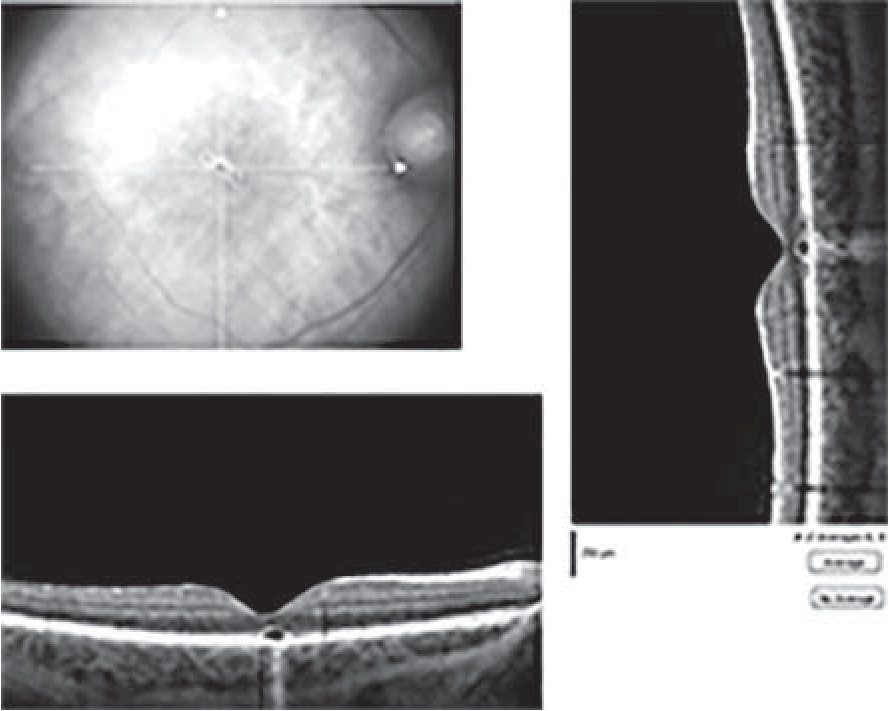

Острота зрения правого глаза – 0,6 (рефракция эмметропическая). Вспомогательные органы и передний сегмент глазного яблока без патологии. При кинетической периметрии в центральном поле зрения отмечаются абсолютные и относительные микроскотомы общей площадью 16 мм2. При центральной статической периметрии выявлено снижение световой чувствительности сетчатки в центральных отделах. При офтальмоскопии обнаружен пигментированный очаг в парафовеолярной области (рис. 1).

Рис. 1. Глазное дно пациента через 3 месяца после поражения лазерным излучением (лазерной указкой). В парафовеолярной области определяются точечные пигментные включения, острота зрения – 0,6

По данным ОКТ и СЛО выявлен дефект наружных слоев пигментного эпителия сетчатки (рис. 2).

Рис. 2. Изображения результатов инфракрасной офтальмоскопии и оптической когерентной томографии пациента через 3 месяца после поражения лазерным излучением (лазерной указкой). В центре фовеа определяется участок атрофии пигментного эпителия и слоя фоторецепторов